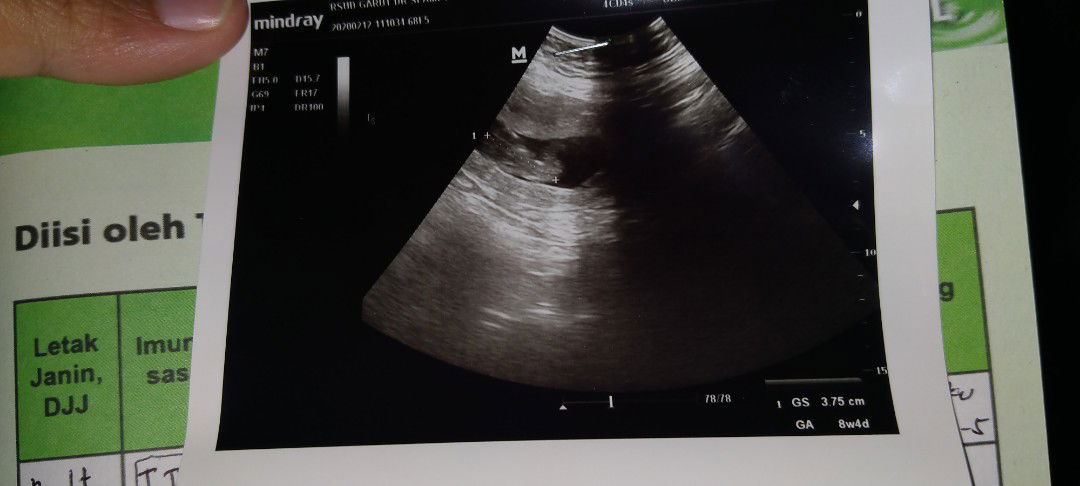

usg

Alhamdulillah sehat

blm usg

Belum di usg tpi menurut bunda dari liat poto ini bisa di tebak ga jenis kelamin nya..

Bun jadi wory liat hsil usg,, klow mnrut hpht kn skrng usia kandungan hrusnya 13 minggu, tp di usg usia nya bru 8 week, trus ktany janin nya kecil trus air ketuban nya sdikit, disini ada bunda yg ngalamin kaya saya,,, trus minta saran nya...

bun kalow mau di usg usia berapa week yah???